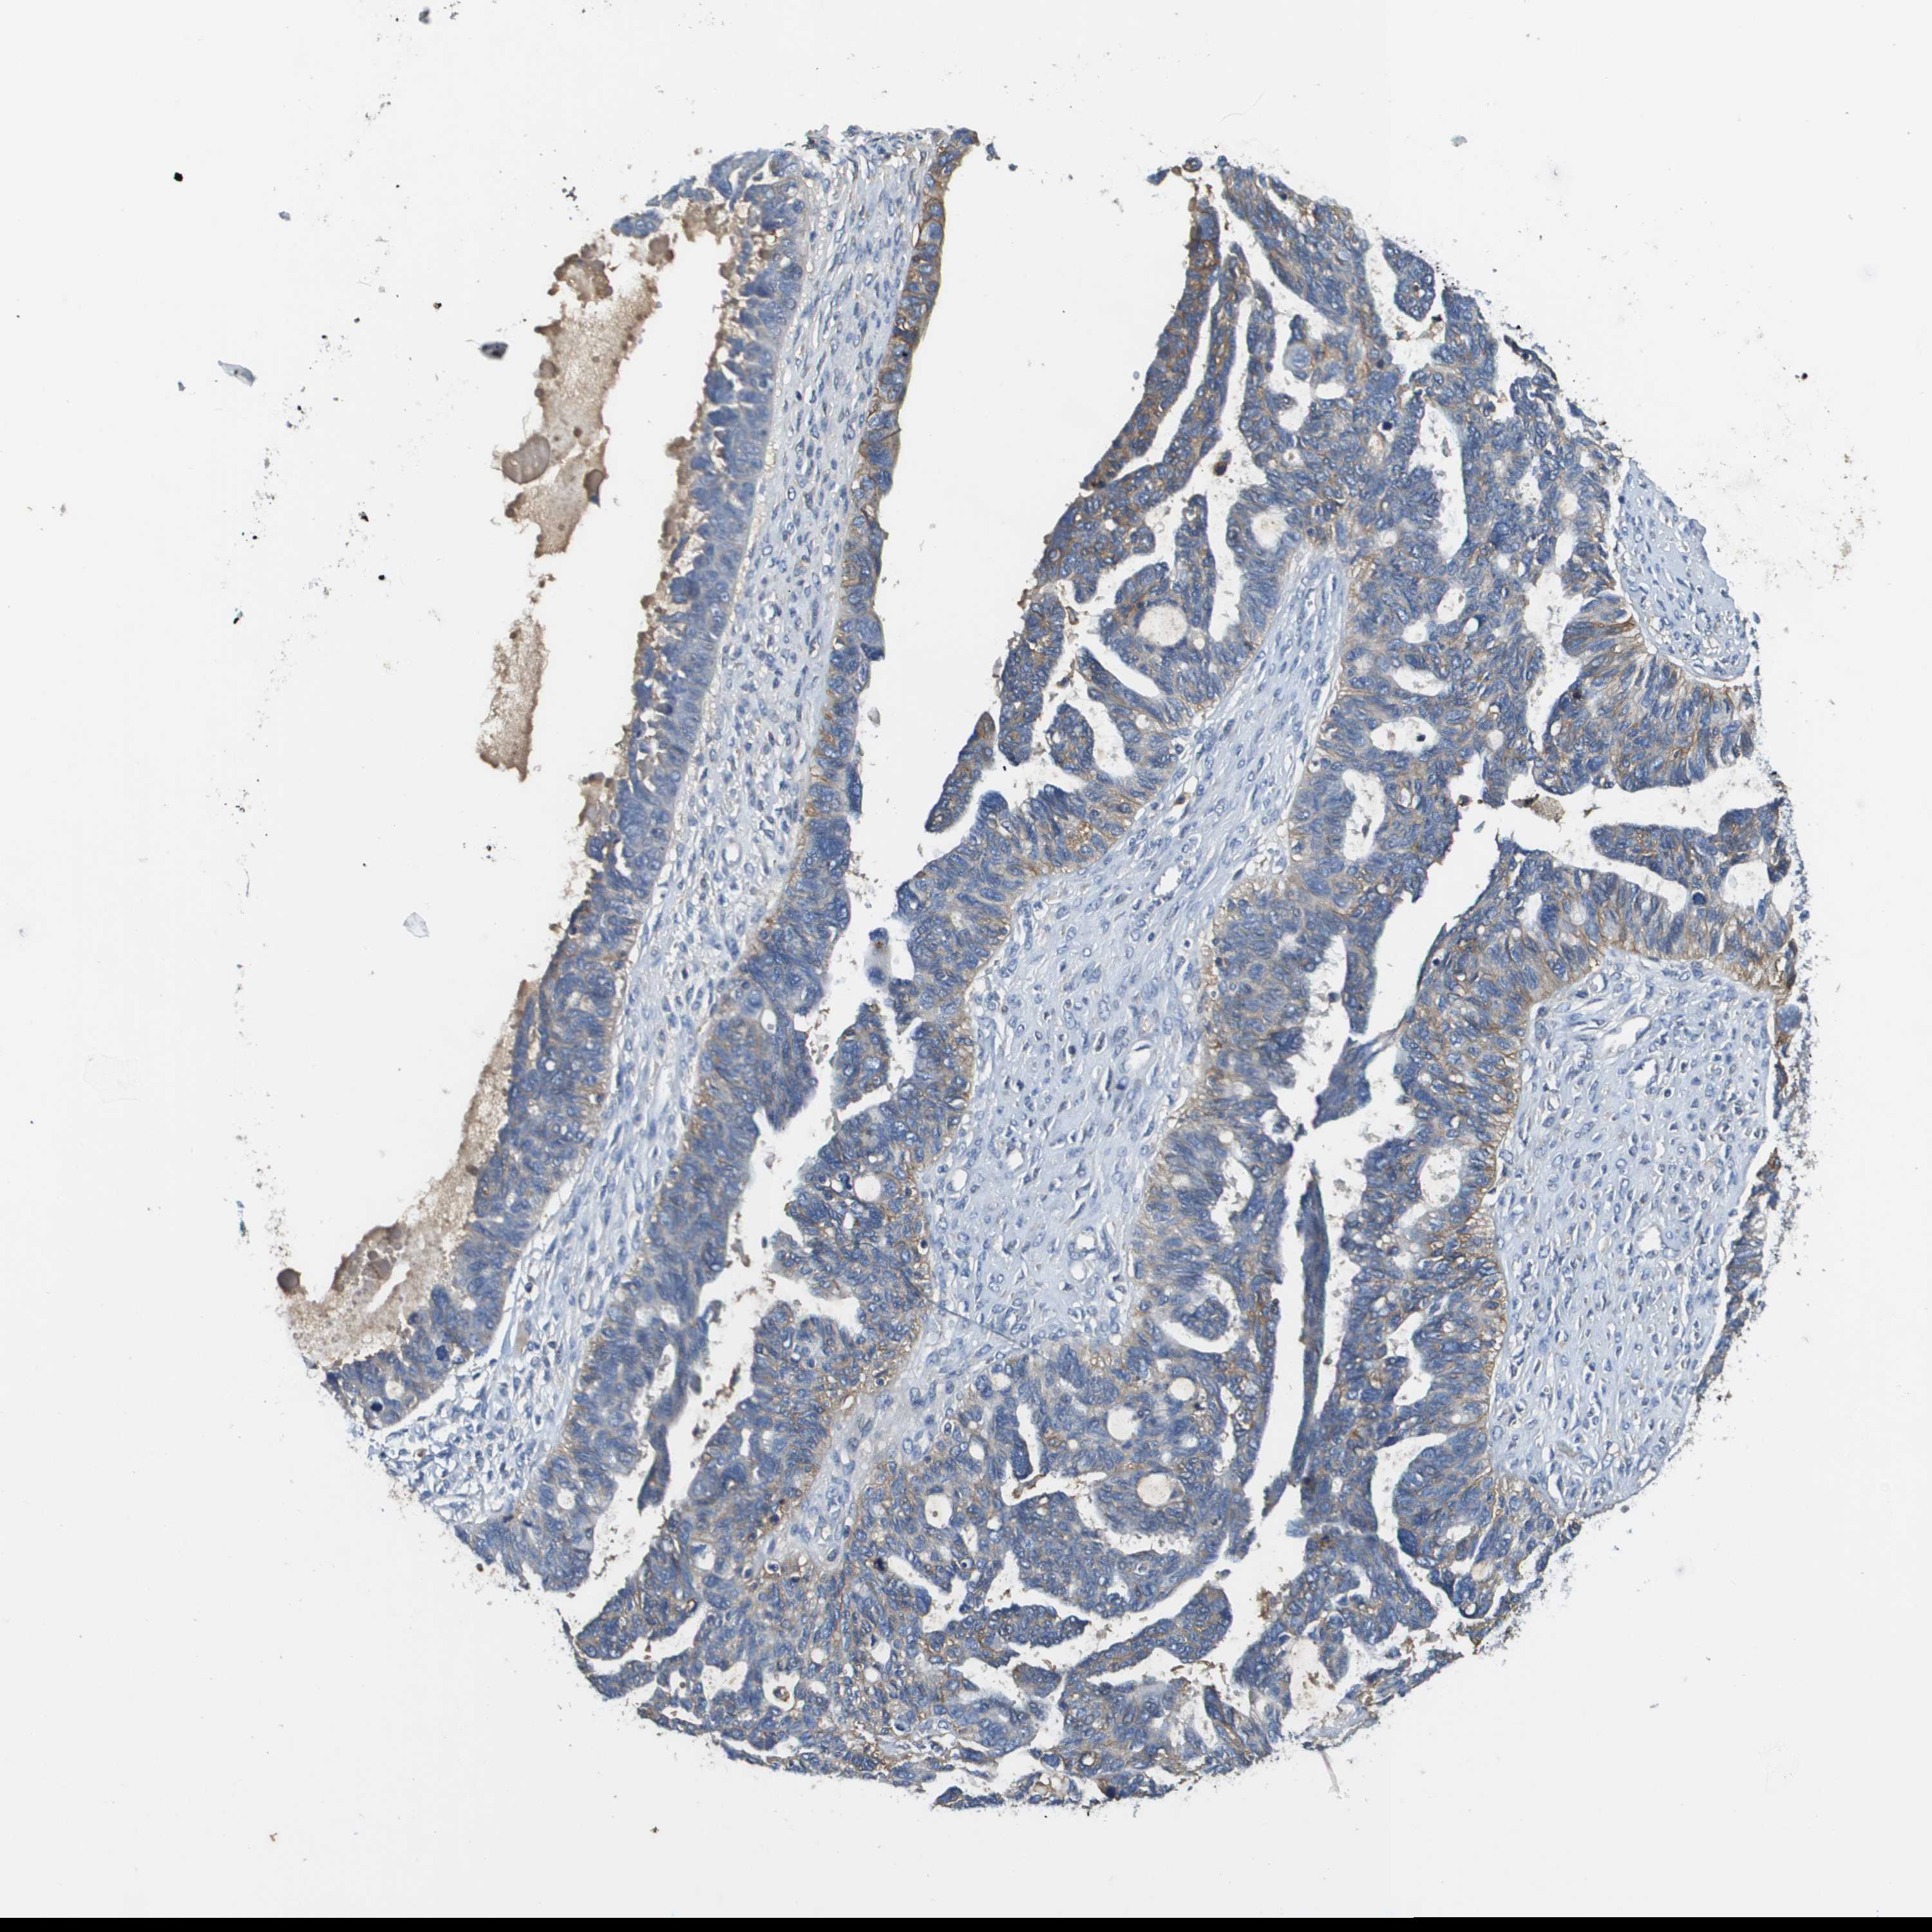

OVARIAN CANCER - Protein expressioni

A mouse-over function shows sample information and annotation data. Click on an image to view it in a full screen mode. Samples can be filtered based on level of antibody staining by selecting one or several of the following categories: high, medium, low and not detected. The assay and annotation is described here.

Note that samples used for immunohistochemistry by the Human Protein Atlas do not correspond to samples in the TCGA dataset.

Antibody stainingi

Antibody staining in the annotated cell types in the current human tissue is reported as not detected, low, medium, or high, based on conventional immunohistochemistry profiling in selected tissues. This score is based on the combination of the staining intensity and fraction of stained cells.

Each image is clickable and will lead to virtual microscopy that enables deeper exploration of all samples and also displays staining intensity scores, fraction scores and subcellular localization as well as patient and tissue information for each sample.

Antibody HPA021451

Antibody CAB017490

Staining

High

Medium

Low

Not detected

Intensity

Strong

Moderate

Weak

Negative

Quantity

>75%

75%-25%

<25%

None

Location

Nuclear

Cytoplasmic/membranous

Cytoplasmic/membranous,nuclear

Cystadenocarcinoma, serous, NOS